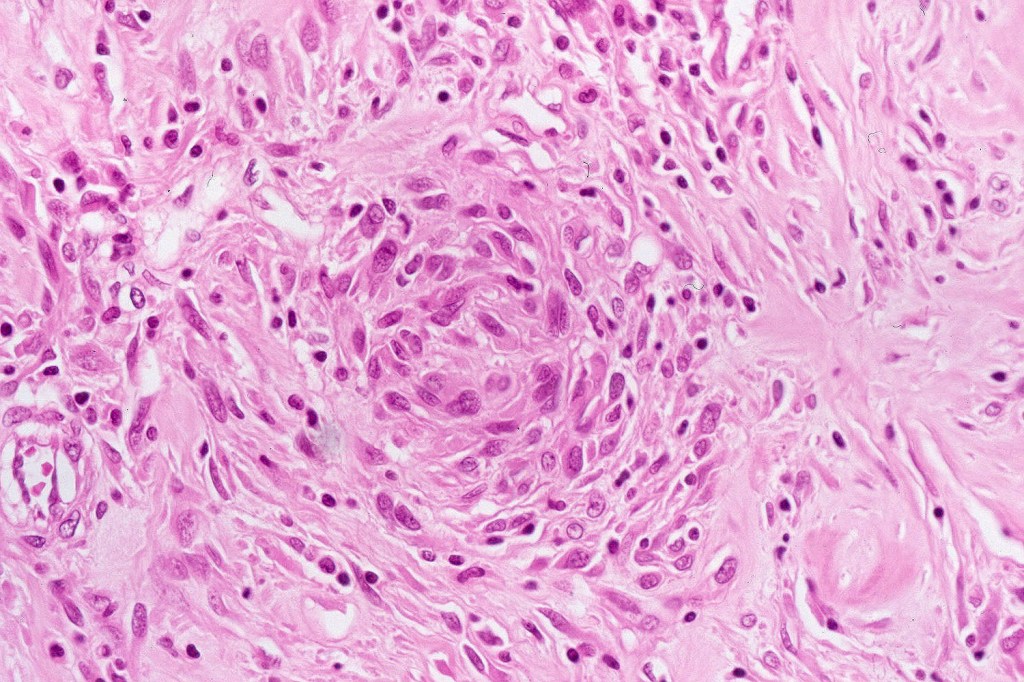

Atpical blue nevus

This is exceedingly rare and the diagnosis should be used very sparingly. It is likely quite benign although very occasionally, a sentinel node biopsy is positive. Great care must be taken to make sure that a blue nevus-like melanoma isn’t missed. It shows the low power features of a blue nevus but high power scrutiny reaveals pleomorphism, nuclear hyperchromatism and increased mitotic activiy (<1 sq mm). Abnormal mitoses are absent as is necrosis. Perineural involvement can be seen but lymphovascular invasion is absent.